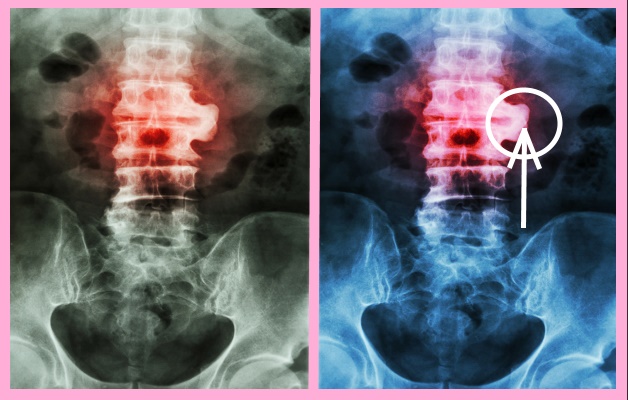

Чтобы уточнить диагноз, после беседы, визуального и пальпаторного обследования больного отправляют на аппаратную диагностику:

- Рентгенографию – показывает присутствие и размер остеофитов, изменение плотности кости тел позвонков, размер щели между телами позвонков (местонахождение межпозвонкового диска), клювообразное срастание остеофитов (спондилез на фоне остеохондроза).